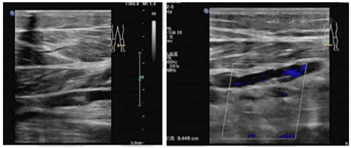

双下肢深静脉彩色多普勒超声检查:右侧小腿肌间静脉血栓形成(不完全阻塞)左侧小腿肌间静脉血栓形成(图3)。